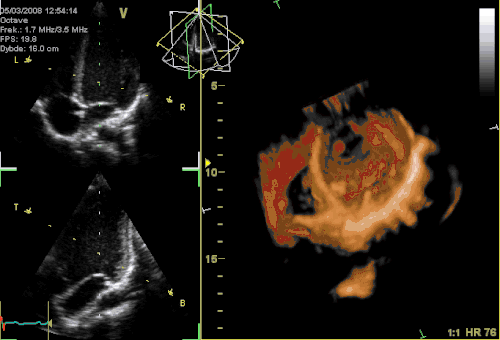

Three-dimensional echocardiography

Three-dimensional echocardiography (also known as four-dimensional echocardiography when the picture is moving) is possible using a matrix array ultrasound probe and an appropriate processing system. It enables detailed anatomical assessment of cardiac pathology, particularly valvular defects,[12] and cardiomyopathies.[13] The ability to slice the virtual heart in infinite planes in an anatomically appropriate manner and to reconstruct three-dimensional images of anatomic structures make it unique for the understanding of the congenitally malformed heart.[14] Real-time three-dimensional echocardiography can be used to guide the location of bioptomes during right ventricular endomyocardial biopsies, placement of catheter-delivered valvular devices, and in many other intraoperative assessments.[15]

Three-dimensional echocardiography technology may feature anatomical intelligence, or the use of organ-modeling technology, to automatically identify anatomy based on generic models. All generic models refer to a dataset of anatomical information that uniquely adapts to variability in patient anatomy to perform specific tasks. Built on feature recognition and segmentation algorithms, this technology can provide patient-specific three-dimensional modeling of the heart and other aspects of the anatomy, including the brain, lungs, liver, kidneys, rib cage, and vertebral column.[16]